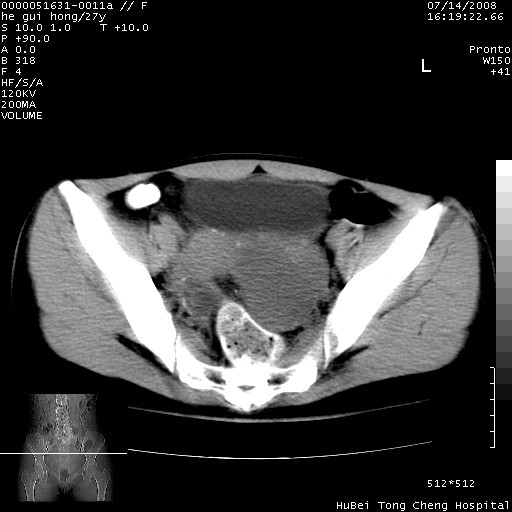

以下是引用杀毒软件在2008-7-20 8:03:00的发言:[br]支持双侧卵巢囊腺瘤可能性大!

以下是引用zjzjr在2008-7-20 13:36:00的发言:[br]双侧附件囊腺瘤可能性大!